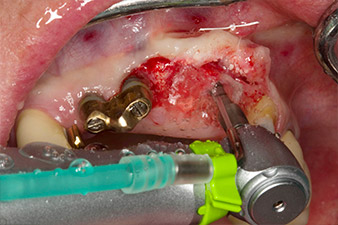

След първичното оздравяване, меките тъкани са оформени посредством базално разположения мост. Два месеца по-късно, обработваното поле е изложено на палатинална алвеоларна инцизия (Фиг 2). Размерите на алвеоларната кост са достатъчни в позиция 22. Фигури 2 и 4 показват препарацията на имплантното ложе, нарязващия винт и имплатирането, използвайки Implantmed.

Новият имплантологичен мотор е използван с подходящите обратни наконечници на W&H.

С цел да се компенсира периодонталната загуба на кост и да се постигне естетически добър резултат, имплантирането е комбинирано с водена костна регенерация (GBR) с ксеногенен заместващ материал и колагенова мембрана (Фиг. 5 и 6).